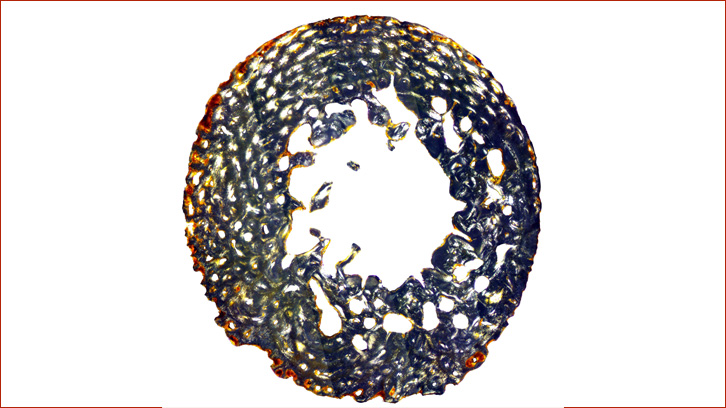

Los resultados son reveladores: los huesos de los individuos pretérmino y de los neonatos presentan una mineralización muy elevada, entre un 60% y un 80% de la sección transversal. Este patrón refleja el proceso normal de mineralización del esqueleto antes del nacimiento. En concreto, aquellos individuos que se encuentran en etapa de desarrollo a término y hasta el primer mes de vida son los que presentan los valores más altos.

Después del primer mes, cuando el bebé ya depende de sus propios procesos metabólicos, esta mineralización disminuye y deja una impronta visible al microscopio. Esto permite, por primera vez en el estudio de la microestructura ósea, determinar si un individuo ha llegado al periodo a término y diferenciarlo del periodo postnatal, una cuestión especialmente compleja en bioarqueología.